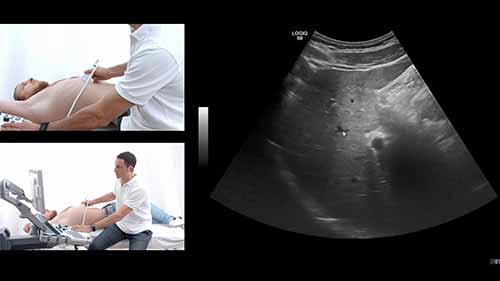

三维四维胎儿超声影像

学会使用超声系统,在2D胎儿影像的基础上,进行3D/4D超声扫描,编辑3D/4D影像。